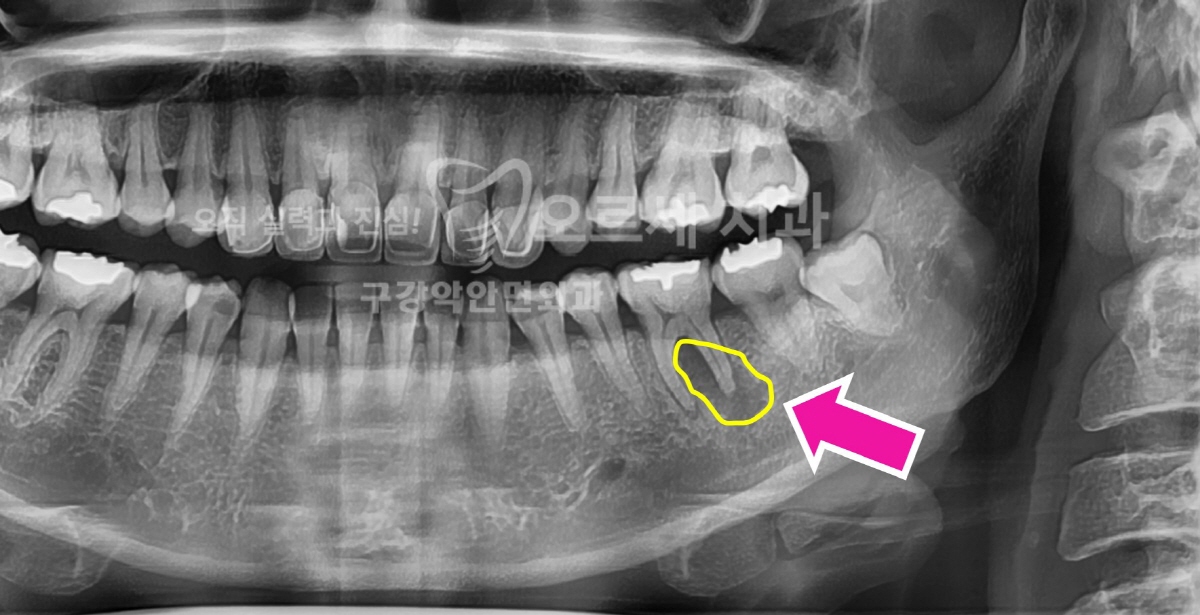

가능하다면 20대에는 발치하는 것이 좋다는 사랑니, 내게 있는 것이 알고 있어도 막상 치과를 향해 발걸음을 떼기가 쉽지 않으시죠. 잇몸 염증과 통증, 심한 경우 앞에 어금니 충치까지 퍼뜨리는 사랑니는 거의 대부분 빼야 하는 경우가 많습니다. 역삼 근처에서 쉽게 찾아올 수 있는 저희 치과에서는 국제구강악안면외과 전문의 원장님께서 직접 누운 매복 사랑니 발치를 진행하고 계신데요. 간혹 신경 손상 등의 합병증 얘기를 다니던 치과에서 듣고 차일피일 발치를 미루다 더 큰 문제를 안고 오시는 경우도 있습니다. 그래서 많은 경험 상 가능하다면 제대로 나와 있는 경우가 아니면 거의 대부분의 매복 사랑니는 빼는 것이 낫다는 의견입니다. 양쪽 아래 사랑니가 있다고 해서 하루 만에 모두 발치하는 경우는 많지 않고요.. 대부..